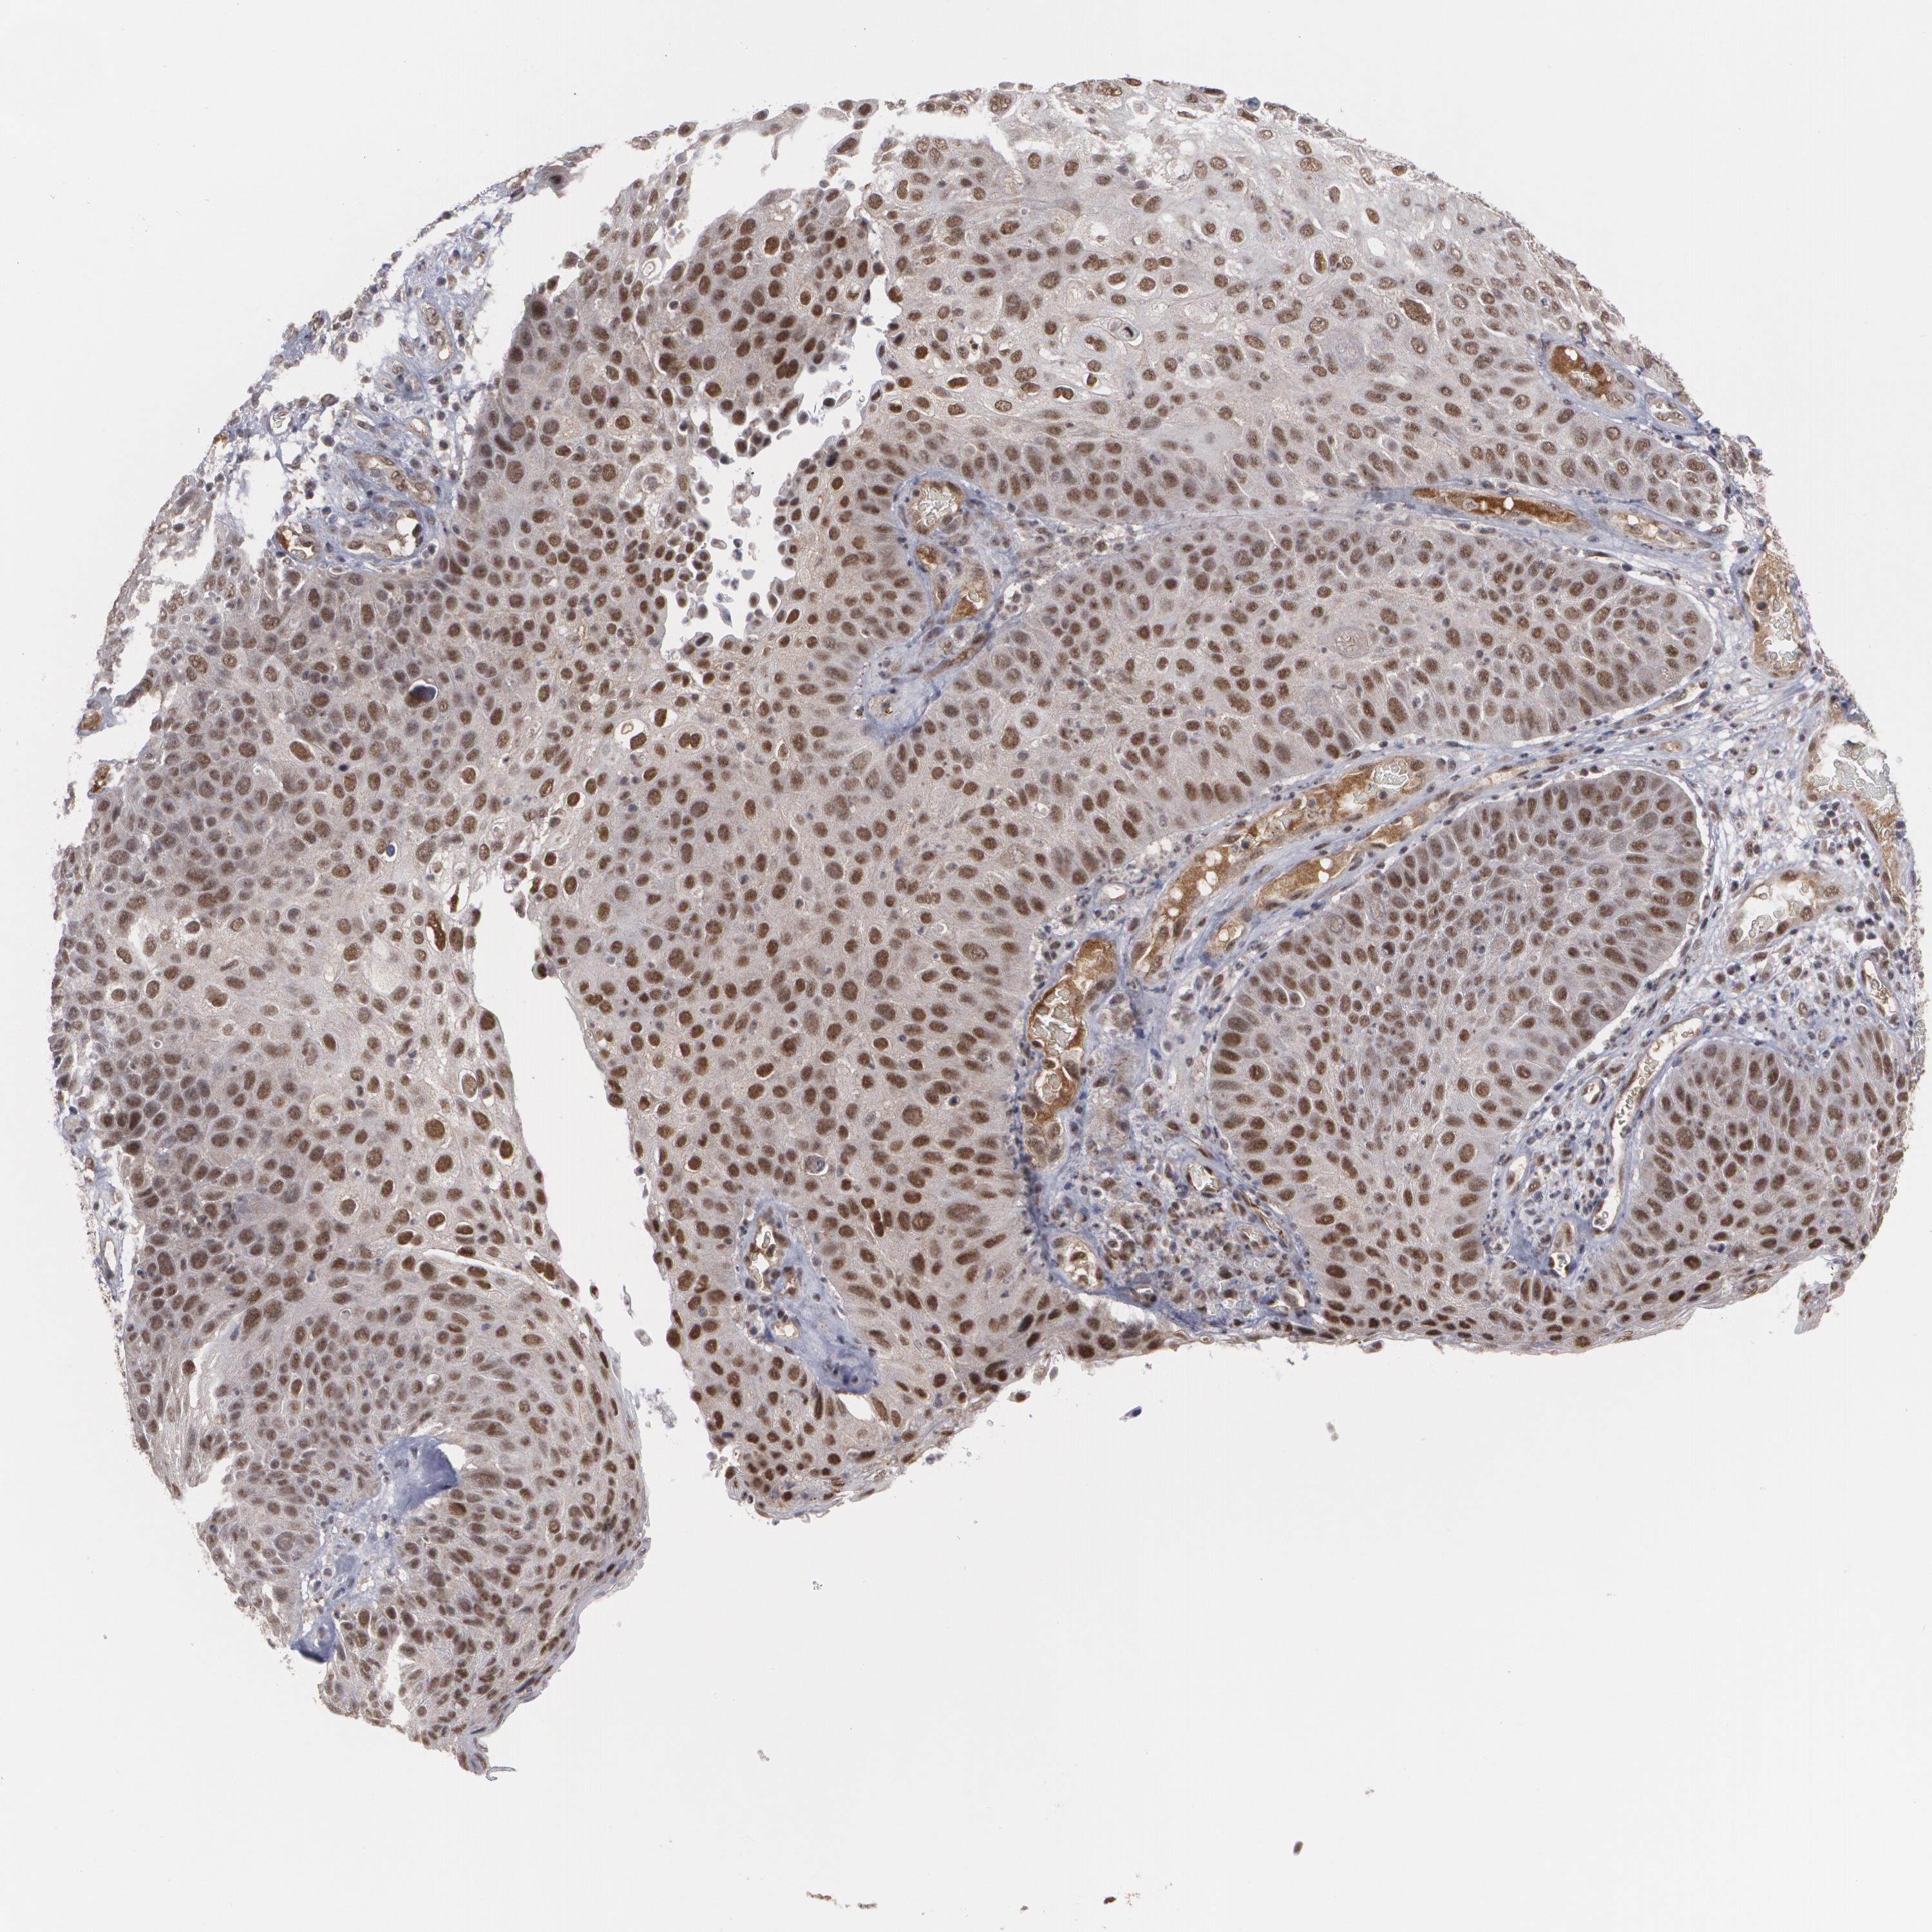

SKIN CANCER - Protein expressioni

A mouse-over function shows sample information and annotation data. Click on an image to view it in a full screen mode. Samples can be filtered based on level of antibody staining by selecting one or several of the following categories: high, medium, low and not detected. The assay and annotation is described here.

Antibody staining in the annotated cell types in the current human tissue is reported as not detected, low, medium, or high, based on conventional immunohistochemistry profiling in selected tissues. This score is based on the combination of the staining intensity and fraction of stained cells.

Each image is clickable and will lead to virtual microscopy that enables deeper exploration of all samples and also displays staining intensity scores, fraction scores and subcellular localization as well as patient and tissue information for each sample.

Antibody HPA001552

Antibody HPA001846

Staining

Medium

Intensity

Moderate

Location

Nuclear

Squamous cell carcinoma, NOS

Basal cell carcinoma